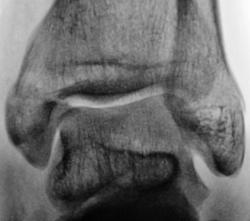

Дорогие друзья, может быть я чего- нибудь не понял, но такое впечатление, что после репозиции стало хуже, чем до неё( по видимому, смещение отломка внутренней лодыжкм кпереди стало более выраженное).

Произведена репозиция отломков и наложена гипсовая повязка.

Ваше мнение уважаемые коллеги?

2х лодыжечный перелом впринципе и до репозиции было хорошо видно, удачно гипс наложили, хорошо хоть дело до подвывиха ни дошло. Безобразие